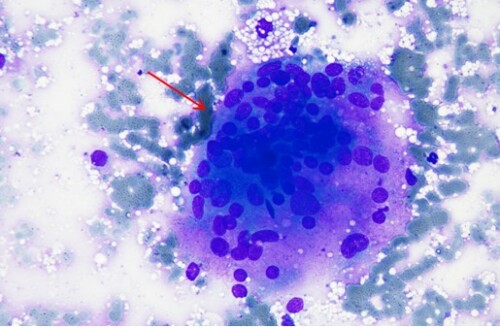

Un cas de cryptococcose féline

Saton est un chat européen mâle castré de 7 ans, présenté en consultation pour de multiples masses sous cutanées sur l’abdomen et hypertrophie des nœuds lymphatiques inguinaux.